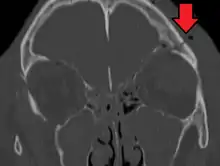

A basilar skull fracture as seen on CT

Basilar skull fractures include breaks in the posterior skull base or anterior skull base. The former involve the occipital bone, temporal bone, and portions of the sphenoid bone; the latter, superior portions of the sphenoid and ethmoid bones. The temporal bone fracture is encountered in 75% of all basilar skull fractures and may be longitudinal, transverse or mixed, depending on the course of the fracture line in relation to the longitudinal axis of the pyramid.[5]